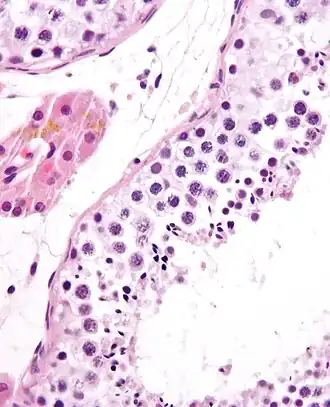

![]() Um túbulo seminífero, com as células da linha germinativa. Coloração H&E.

A espermatogénese ocorre em várias estruturas do sistema reprodutor masculino. As etapas iniciais têm lugar nos testículos, passando depois para o epidídimo, onde os gâmetas em desenvolvimento sofrem maturação e são armazenados até à ejaculação. Os túbulos seminíferos dos testículos são o ponto de partida do processo, onde as células basais adjacentes à parede interior do túbulo se dividem numa orientação centrípeta—começando nas paredes e progredindo até ao lúmen—produzindo espermatozóides imaturos. A maturação tem lugar no epidídimo.

Espermatocitogénese

A rapidez desta etapa é o motivo pelo qual os espermatócitos secundários são raramente vistos em estudos histológicos.